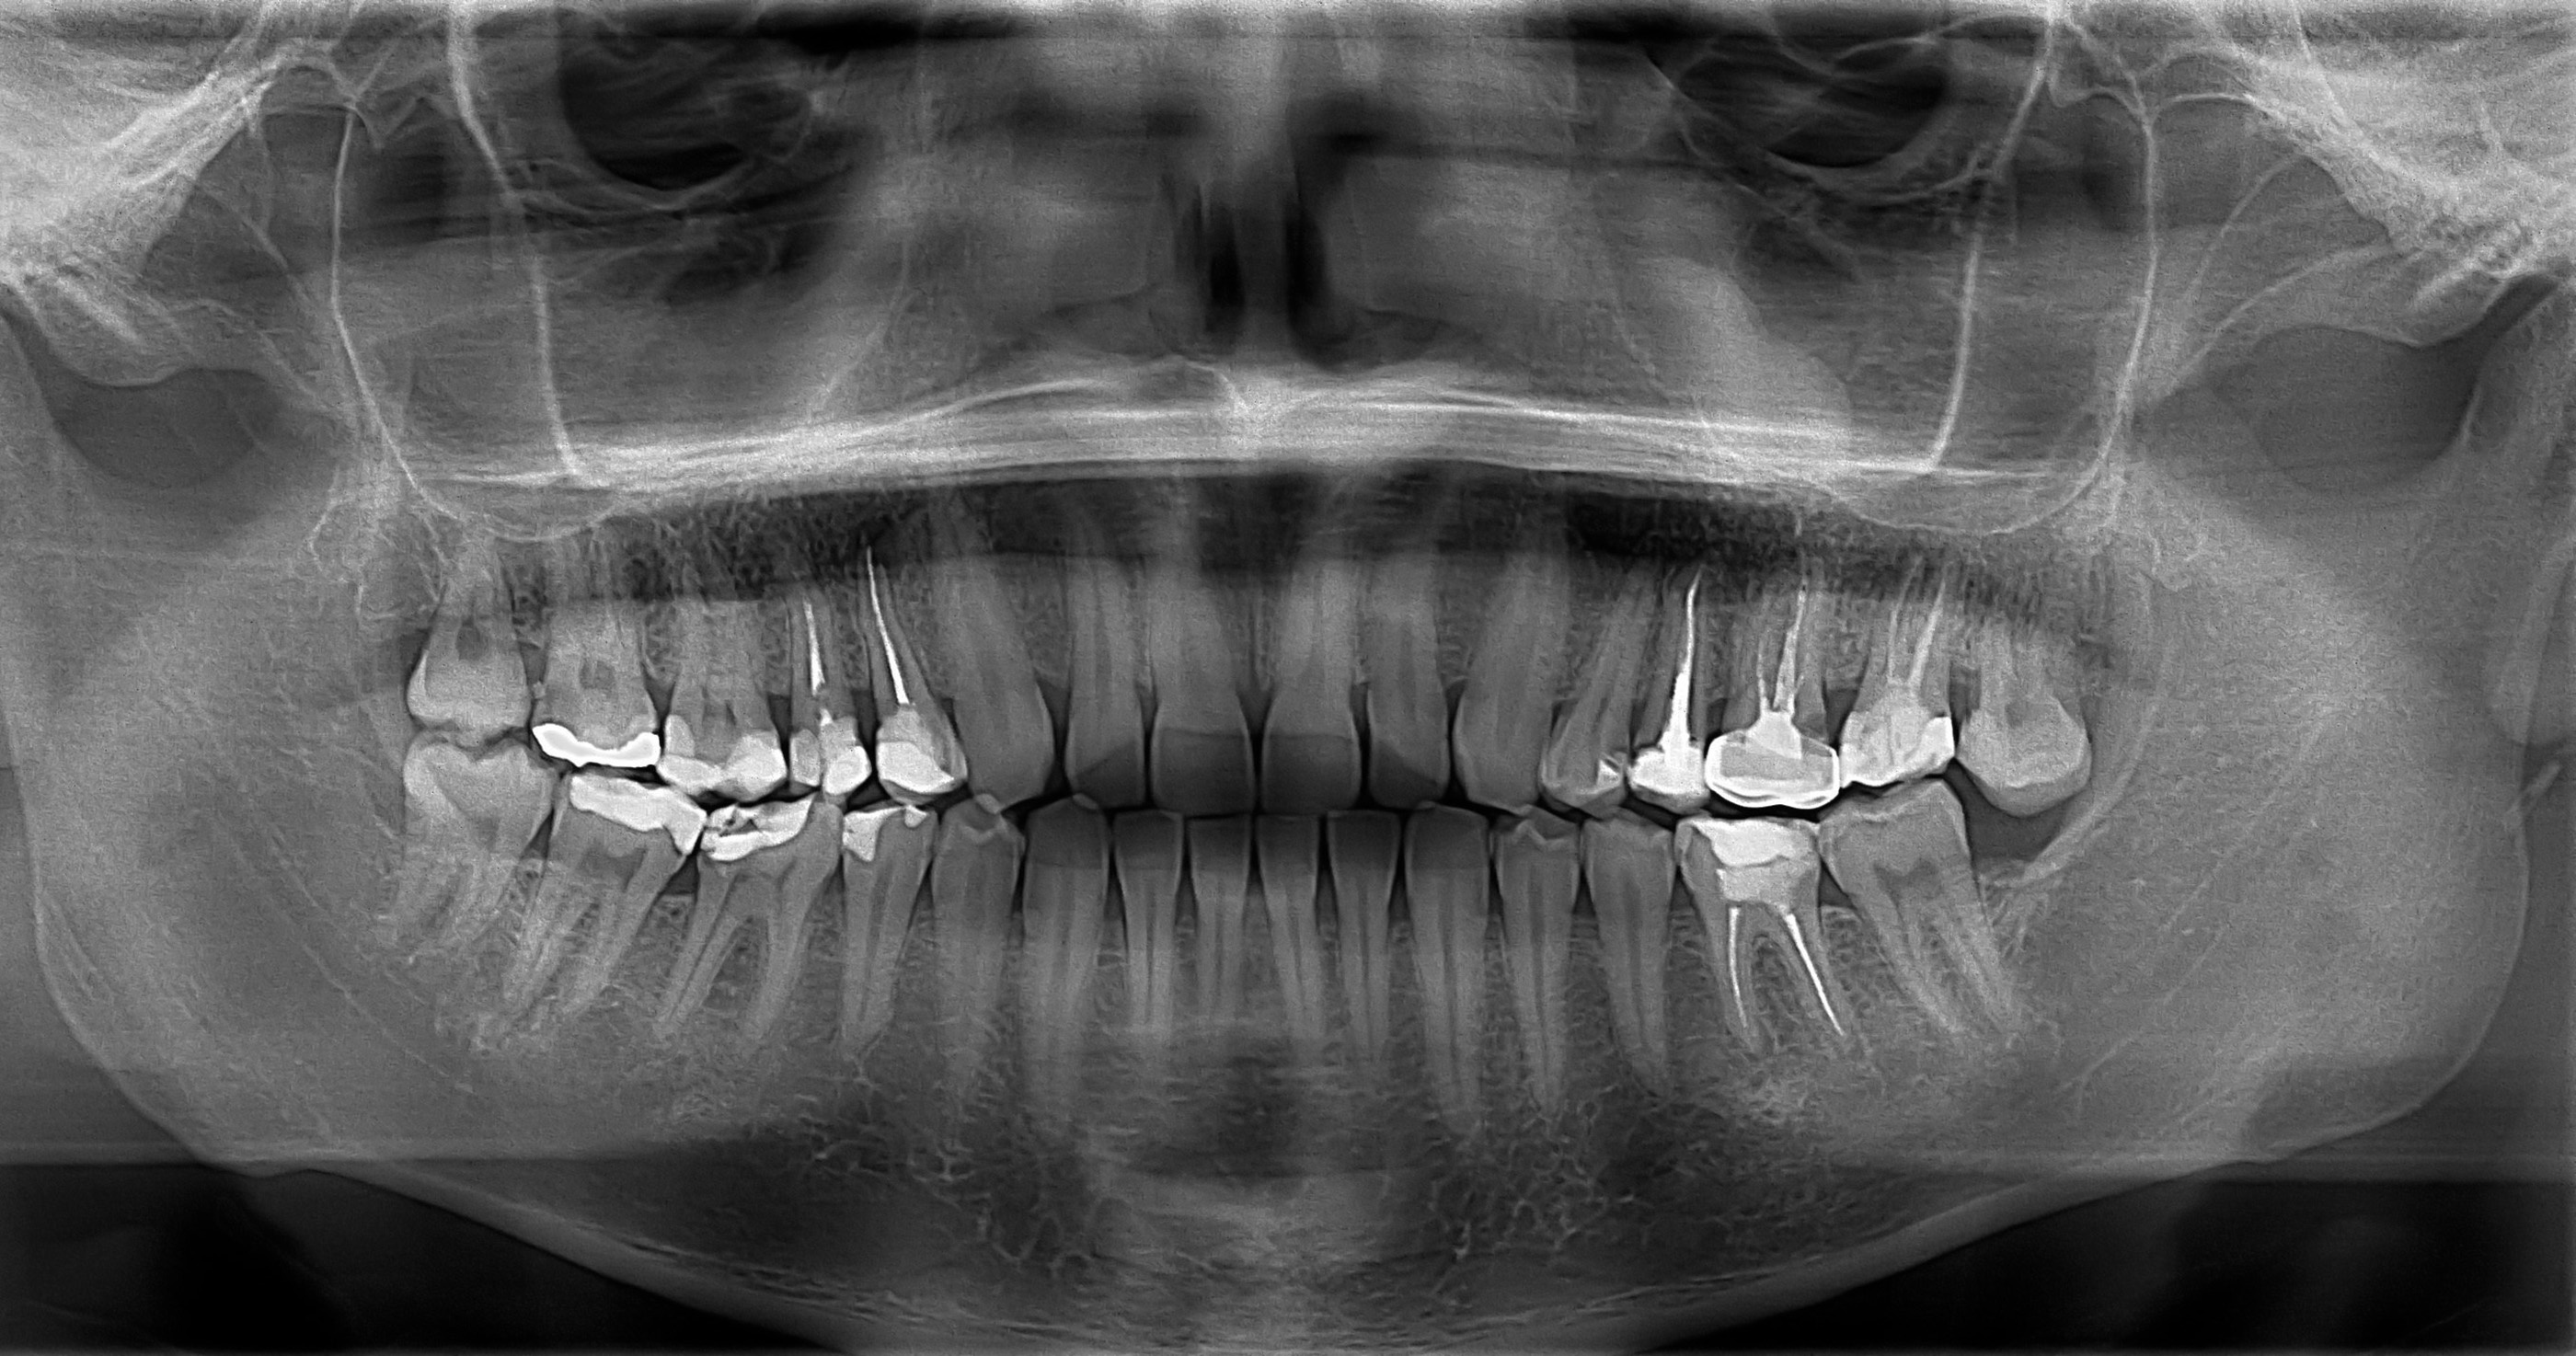

Las radiografías dentales son una herramienta fundamental en la odontología preventiva, ya que permiten detectar a tiempo problemas que no son visibles a simple vista durante una revisión rutinaria. Gracias a estas imágenes, el odontólogo puede observar el interior de los dientes, las raíces, el hueso que los sostiene y la posición de las piezas que aún no han erupcionado, como en el caso de los niños o adolescentes.

Su importancia radica en que facilitan la detección temprana de caries, infecciones, quistes, fracturas o enfermedades periodontales, incluso antes de que el paciente presente síntomas. Esto permite iniciar tratamientos oportunos, menos invasivos y más económicos, evitando complicaciones mayores a largo plazo.

Además, las radiografías son esenciales en la planificación de procedimientos como ortodoncias, extracciones o implantes, pues brindan una visión completa del estado bucal.